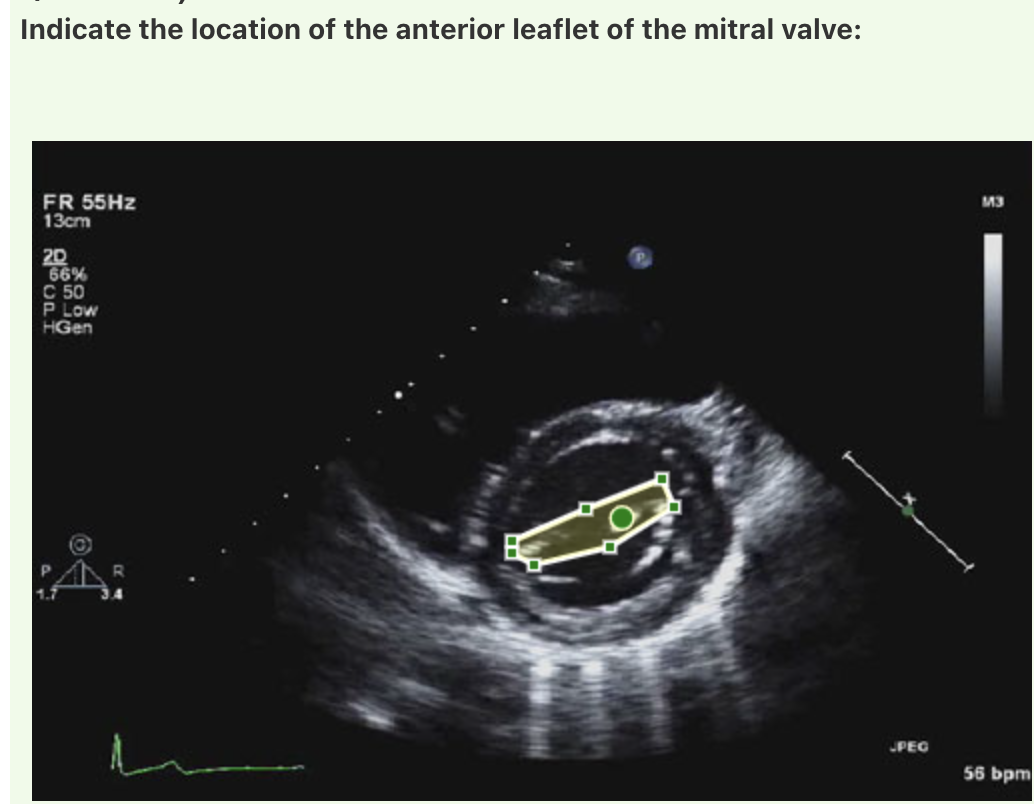

**Answer: Mitral valve**